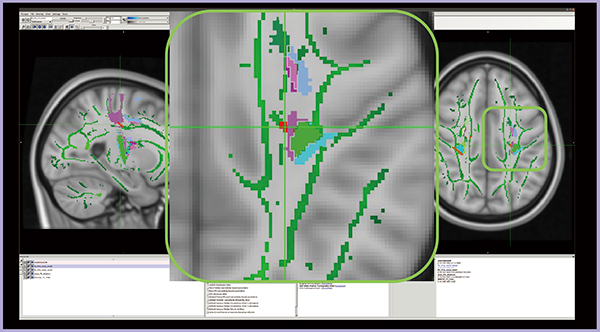

NODDIの統計解析手法として提案されているのが,GBSS(gray matter-based spatial statistics)である。TBSSが白質にスケルトンを設定するのに対し,GBSSでは皮質に灰白質スケルトンを設定し,NODDIのパラメータを空間的正規化する。舌痛症/コントロール群について,ODIをGBSSで解析したところ有意な群間差は認められなかったが,TBSSで広範な異常が見られたMDでは群間差が認められた(図2)。Harvard-Oxford Subcortical Structural Atlasを適用すると,同部位の85%が左扁桃体であり,RDの解析でも同様であった。扁桃体はペインマトリックス(痛み関連脳領域)に関与すると言われており,同部位に群間差が見られたことは妥当性があると考えられる。

図2 GBSSを用いたNODDI解析結果(MD)